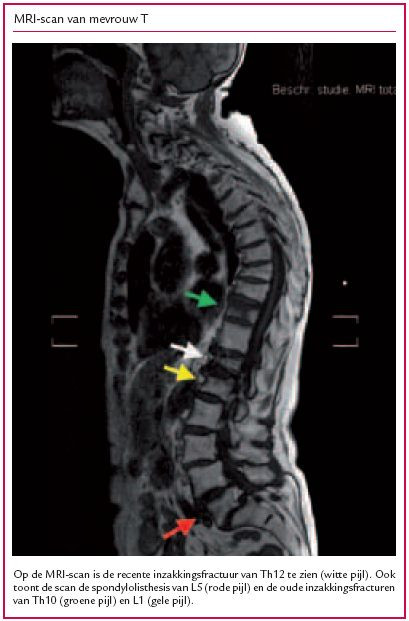

De NHG-Standaard Osteoporose adviseert pijn bij osteoporotische wervelfracturen te bestrijden met medicatie. Soms echter schiet de pijnbestrijding tekort. Een vertebroplastiek of kyfoplastiek lijkt een aantrekkelijk alternatief voor deze patiënten, maar biedt alleen op korte termijn enig…